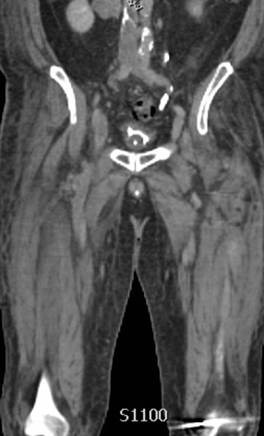

Venografía axial por CT donde se muestra un trombo agudo que va del filtro de VCI  hasta la vena ilíaca interna y externa derecha y la vena ilíaca común izquierda.

Venografía coronaria por CT donde se muestra un trombo agudo que va del filtro de VCI hasta la vena ilíaca interna y externa derecha y la vena ilíaca común izquierda.